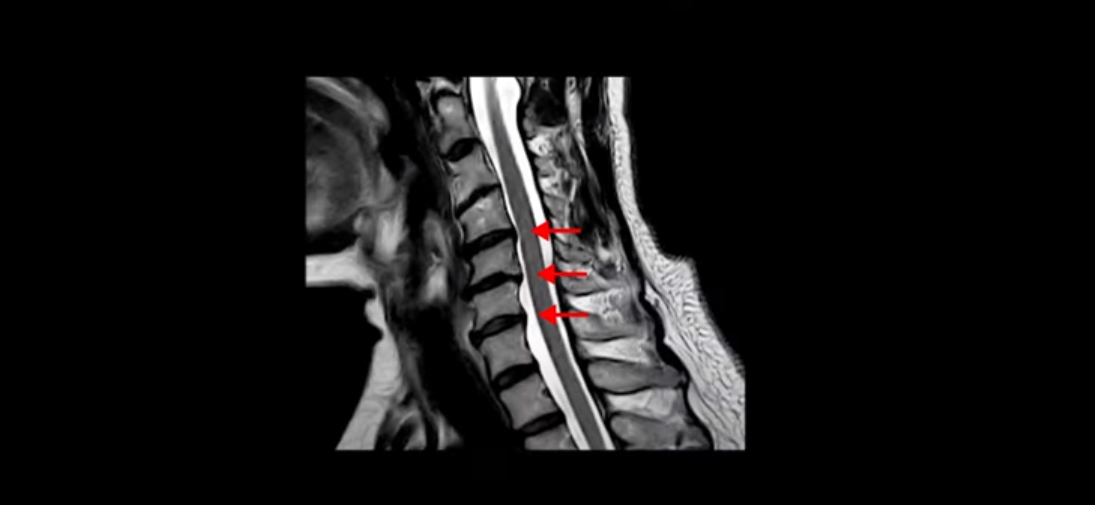

대학병원에 가서 MRI를 찍었는데 거기서도 디스크 증상이 있다고 했어요. 그리고 협착증 이런 게 있다고 했고 치료 방법 소개를 안 해주셨어요. 그냥 운동하라고만 얘기하시고 진통제 약만 주시고 그냥 내보냈어요. 어떻게 운동을 해야 될지도 모르겠고 운동하는 방법을 알려주는 데를 소개를 해주시든지 그냥 종이 보고 운동하라고 하시니까 내가 운동을 어떻게 해요. 혼자서 못하죠.

MRI에서도 보시다시피 여러 마디에 퇴행성 디스크가 있습니다.

이런 걸 협착이라고 부르는 거죠. 이 분의 가장 불편한 증상은 20년간 아픈 만성적인 목통증과 어깨통증, 두통과 눈 통증인데 최근 들어 가증 불편한 증상은 목이 아예 돌아가지 않는 겁니다. 그래서 운전할 때도 사이드 미러를 보려면 몸을 돌리셨다고 하는데요. 주사 효과도 전혀 없고 대학병원에서도 디스크와 협착인데 그냥 약먹고 운동만 하라고 하면 이 환자는 어떻게 해야 할까요?

이 환자분도 아까 X-ray에서 보여드렸듯이 아주 심한 일자목, 거북목이 있고 그 결과로 목의 거의 모든 마디가 다 퇴행이 진행되어 있죠. 즉 거북목은 모든 목질환, 특히 목디스크, 목협착증의 어머니 질환이며 그래서 목디스크를 치료하기 위해서는 반드시 거북목 때문에 짧아지고 뭉치고 굳고 뒤틀린 목 주변 근육들을 잘 치료해줘야 합니다.